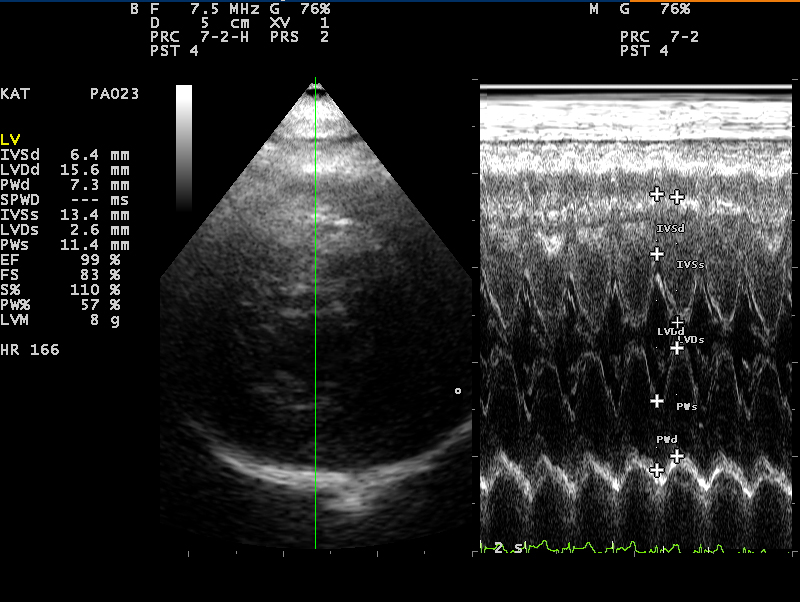

- Hart

85% van de katten met een hoge bloeddruk heeft ook een hartafwijking. De hartspier raakt verdikt door overbelasting waardoor een hartruis en/of een afwijkende hartritme op kan treden. Benauwdheid kan hiervan een vervelend gevolg zijn.